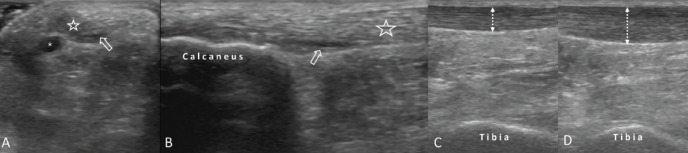

他莫昔芬相关跟腱病变的超声成像和指导。

Ultrasound Imaging and Guidance for Tamoxifen-Associated Achilles Tendinopathy.